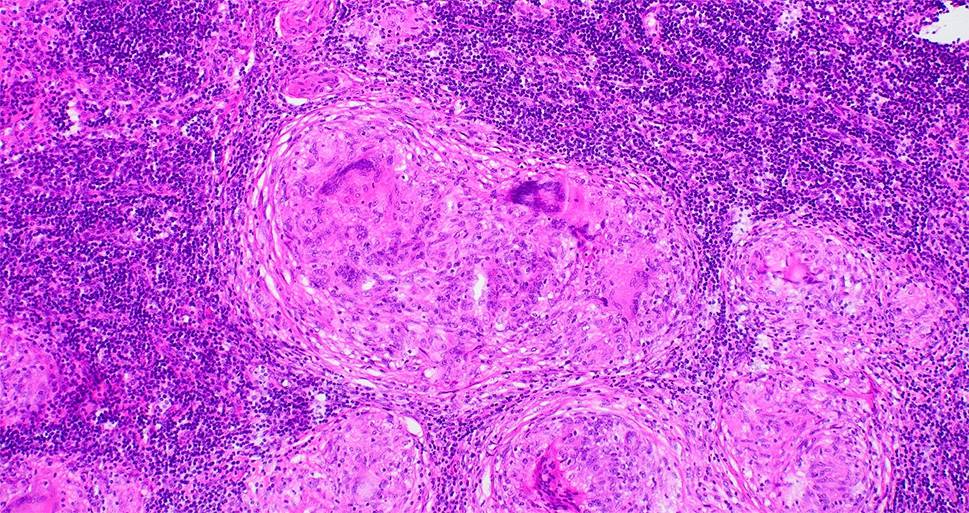

Das histologische Markenzeichen der Sarkoidose ist das Granulom: Es ist meistens nicht nekrotisch, hat einen zentralen Kern aus Makrophagenaggregaten und vielkernigen Riesenzellen und eine äußere Schicht aus locker organisierten Lymphozyten, dendritischen Zellen und gelegentlich B‑Zellen [9]. Bei Unklarheiten sollte eine Färbung auf säurefeste Stäbchen, eine Kultur auf Pilze und Mykobakterien und eine Mycobacterium-tuberculosis-PCR erfolgen (Abb. 1).

Abb. 1

Morphologie des Sarkoidosegranuloms: kompakte, gut geformte Ansammlungen von großen, epitheloiden Makrophagen und vielkernigen Riesenzellen